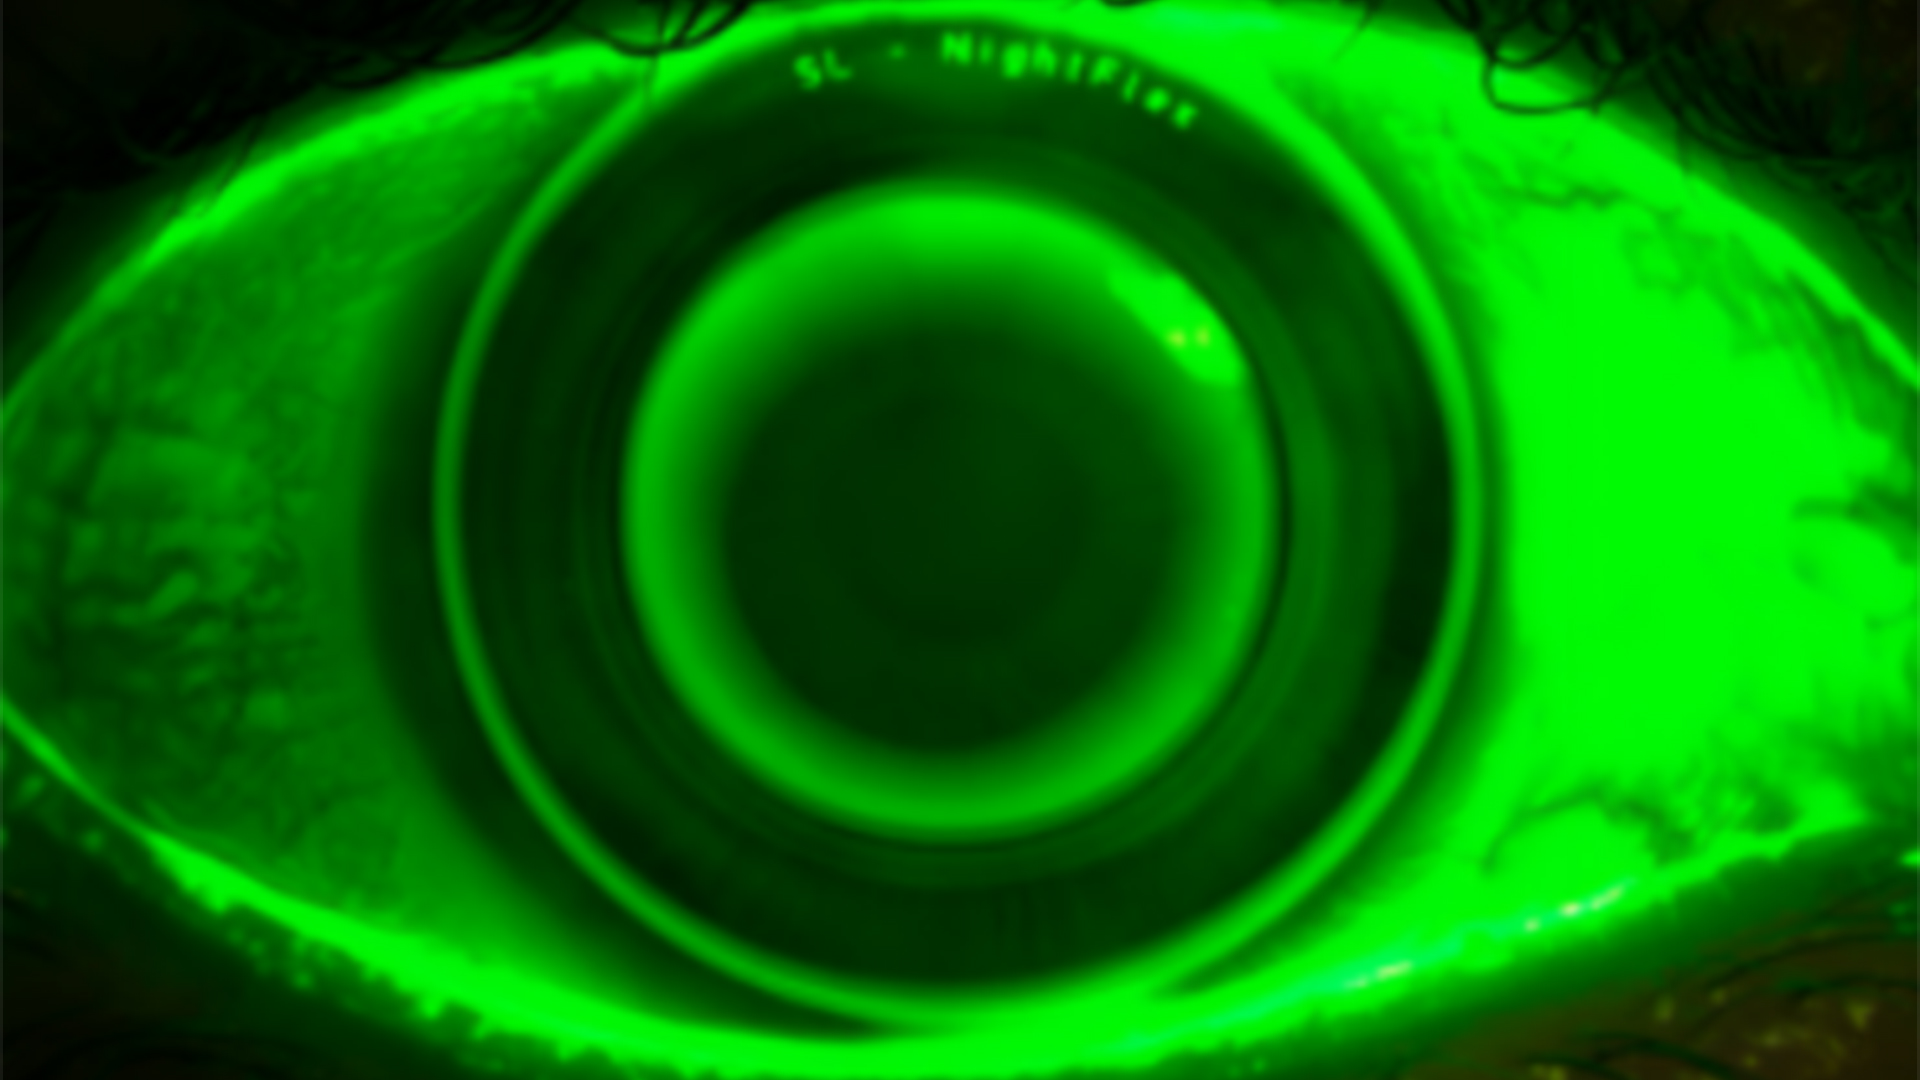

Ortho-K: Troubleshooting und Anpassfälle aus dem Alltag

Stoßen Sie manchmal an die Grenzen von Orthokeratologie Systemen? Ist es für Sie wichtig auch Kinder optimal und im Rahmen eines Myopiemanagements zu versorgen? Dann sind Sie hier genau richtig! Wir verschieben Ihre Grenzen und üben gemeinsam auch die Kleinsten sicher und zum Vorteil der Augengesundheit zu versorgen.